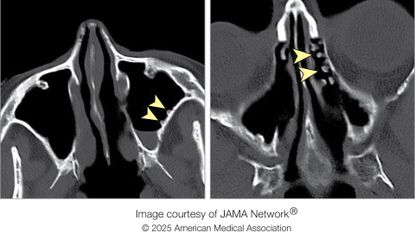

Diagnostic dilemma: A fish bone wandered through a man's abdomen and stabbed his liverA man went to the hospital several times with gut pain and a fever — and it turned out that his relatively common symptoms had an unusual cause.